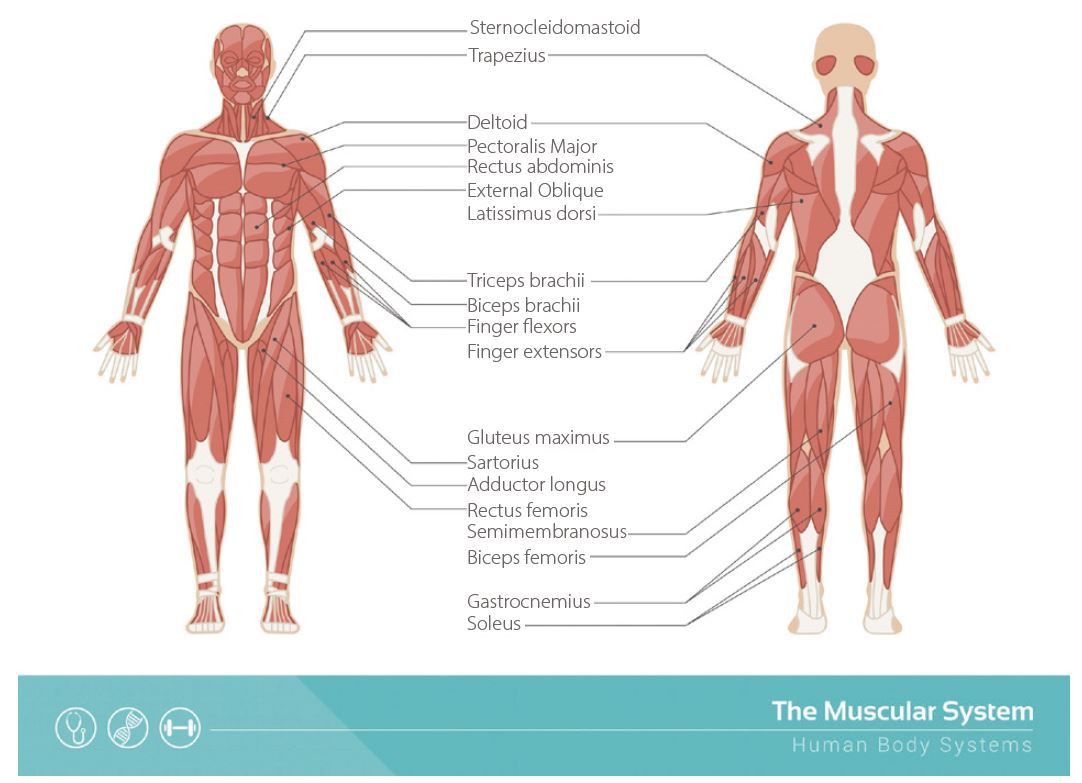

Саркоми м’яких тканин є рідкісними видами раку, які становлять від 1 до 2% усіх ракових захворювань. Це злоякісні пухлини, що розвиваються в сполучній тканині або опорних клітинах. Вони названі на честь типу клітин здорової тканини, на які ракові клітини схожі при перегляді під мікроскопом. Понад 50% сарком м’яких тканин виникають у кінцівках. Вони частіше розвиваються на нижніх кінцівках, ніж на верхніх, особливо на стегні. Існує понад 50 різних типів сарком м’яких тканин (рис. 1). Кількість нових випадків захворювання становить 3,4 на 100 тис. населення на рік, а кількість смертей – 1,3 на 100 тис. населення на рік. Відносна вірогідність прожити 5 років для всіх типів сарком м'яких тканин становить 65%.

Рисунок 1